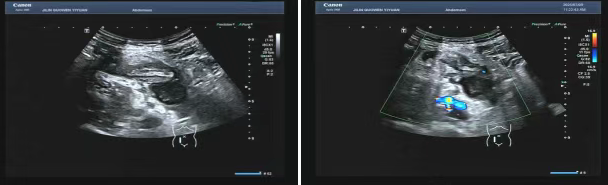

80 歲的張爺爺(化名)因前列腺增生前往國文醫(yī)院就診,泌尿外科為其開具了泌尿系超聲檢查。超聲科醫(yī)生在檢查過程中,憑借敏銳的觀察力,發(fā)現(xiàn)患者右下腹有異?;旌匣芈暟鼔K。醫(yī)生沒有放過這一異常,立即展開進(jìn)一步探查,結(jié)果顯示包塊內(nèi)疑似有闌尾結(jié)構(gòu),且周圍組織存在粘連,還伴有液性暗區(qū)??紤]到老年患者病情往往較為隱匿,癥狀也不典型,醫(yī)生第一時間與臨床醫(yī)生溝通,建議進(jìn)行緊急處理。隨后,經(jīng)過臨床醫(yī)生詳細(xì)檢查,患者迅速辦理住院并接受手術(shù),術(shù)后病理檢查結(jié)果確診為 “闌尾壞疽伴穿孔合并膿腫形成”。

主治醫(yī)生介紹,老年人患闌尾炎時,癥狀常常不典型,很容易被誤診為腸胃炎或其他疾病。張爺爺僅表現(xiàn)出輕微腹脹的癥狀。倘若不是超聲檢查時意外發(fā)現(xiàn),極有可能延誤治療,進(jìn)而引發(fā)感染性休克,甚至危及生命。超聲檢查在這類急腹癥的篩查中,發(fā)揮了至關(guān)重要的作用。

“雖然在泌尿系檢查中發(fā)現(xiàn)闌尾病變屬于意外,但這也得益于我院超聲檢查要求的標(biāo)準(zhǔn)切面掃查,以及絕不放過任何異常的職業(yè)習(xí)慣,才能夠捕捉到這一隱藏的隱患?!?超聲科主任表示。國文醫(yī)院超聲科始終秉持 “全面掃查、精準(zhǔn)診斷” 的理念。近年來,已多次在常規(guī)檢查中發(fā)現(xiàn)早期腫瘤、血管栓塞等意外病變,為眾多患者贏得了寶貴的治療先機(jī)。